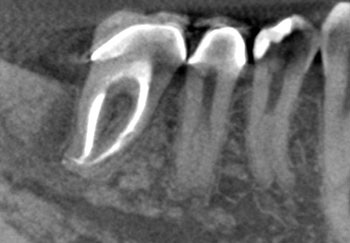

Case 7: A furcation radiolucency

A patient solicited a second opinion after her dentist recommended extraction of #18 because of a suspected VRF, apparently suggested by a midbuccal probing defect.

This tooth had irreversible pulpitis, and RCT was initiated. Examination of the pulp chamber using a microscope did not reveal any cracking. A lateral canal leading to the furcation was identified but could not be negotiated. Hence, this tooth was treated in three visits using a calcium hydroxide intracanal medicament and obturated after resolution of the pocket and bony healing were confirmed.

Fig. 26: Preop CBCT SAG.

Fig. 27: Preop CBCT AX

Fig. 28: Postop CBCT SAG.

Fig. 29: Postop CBCT AX.